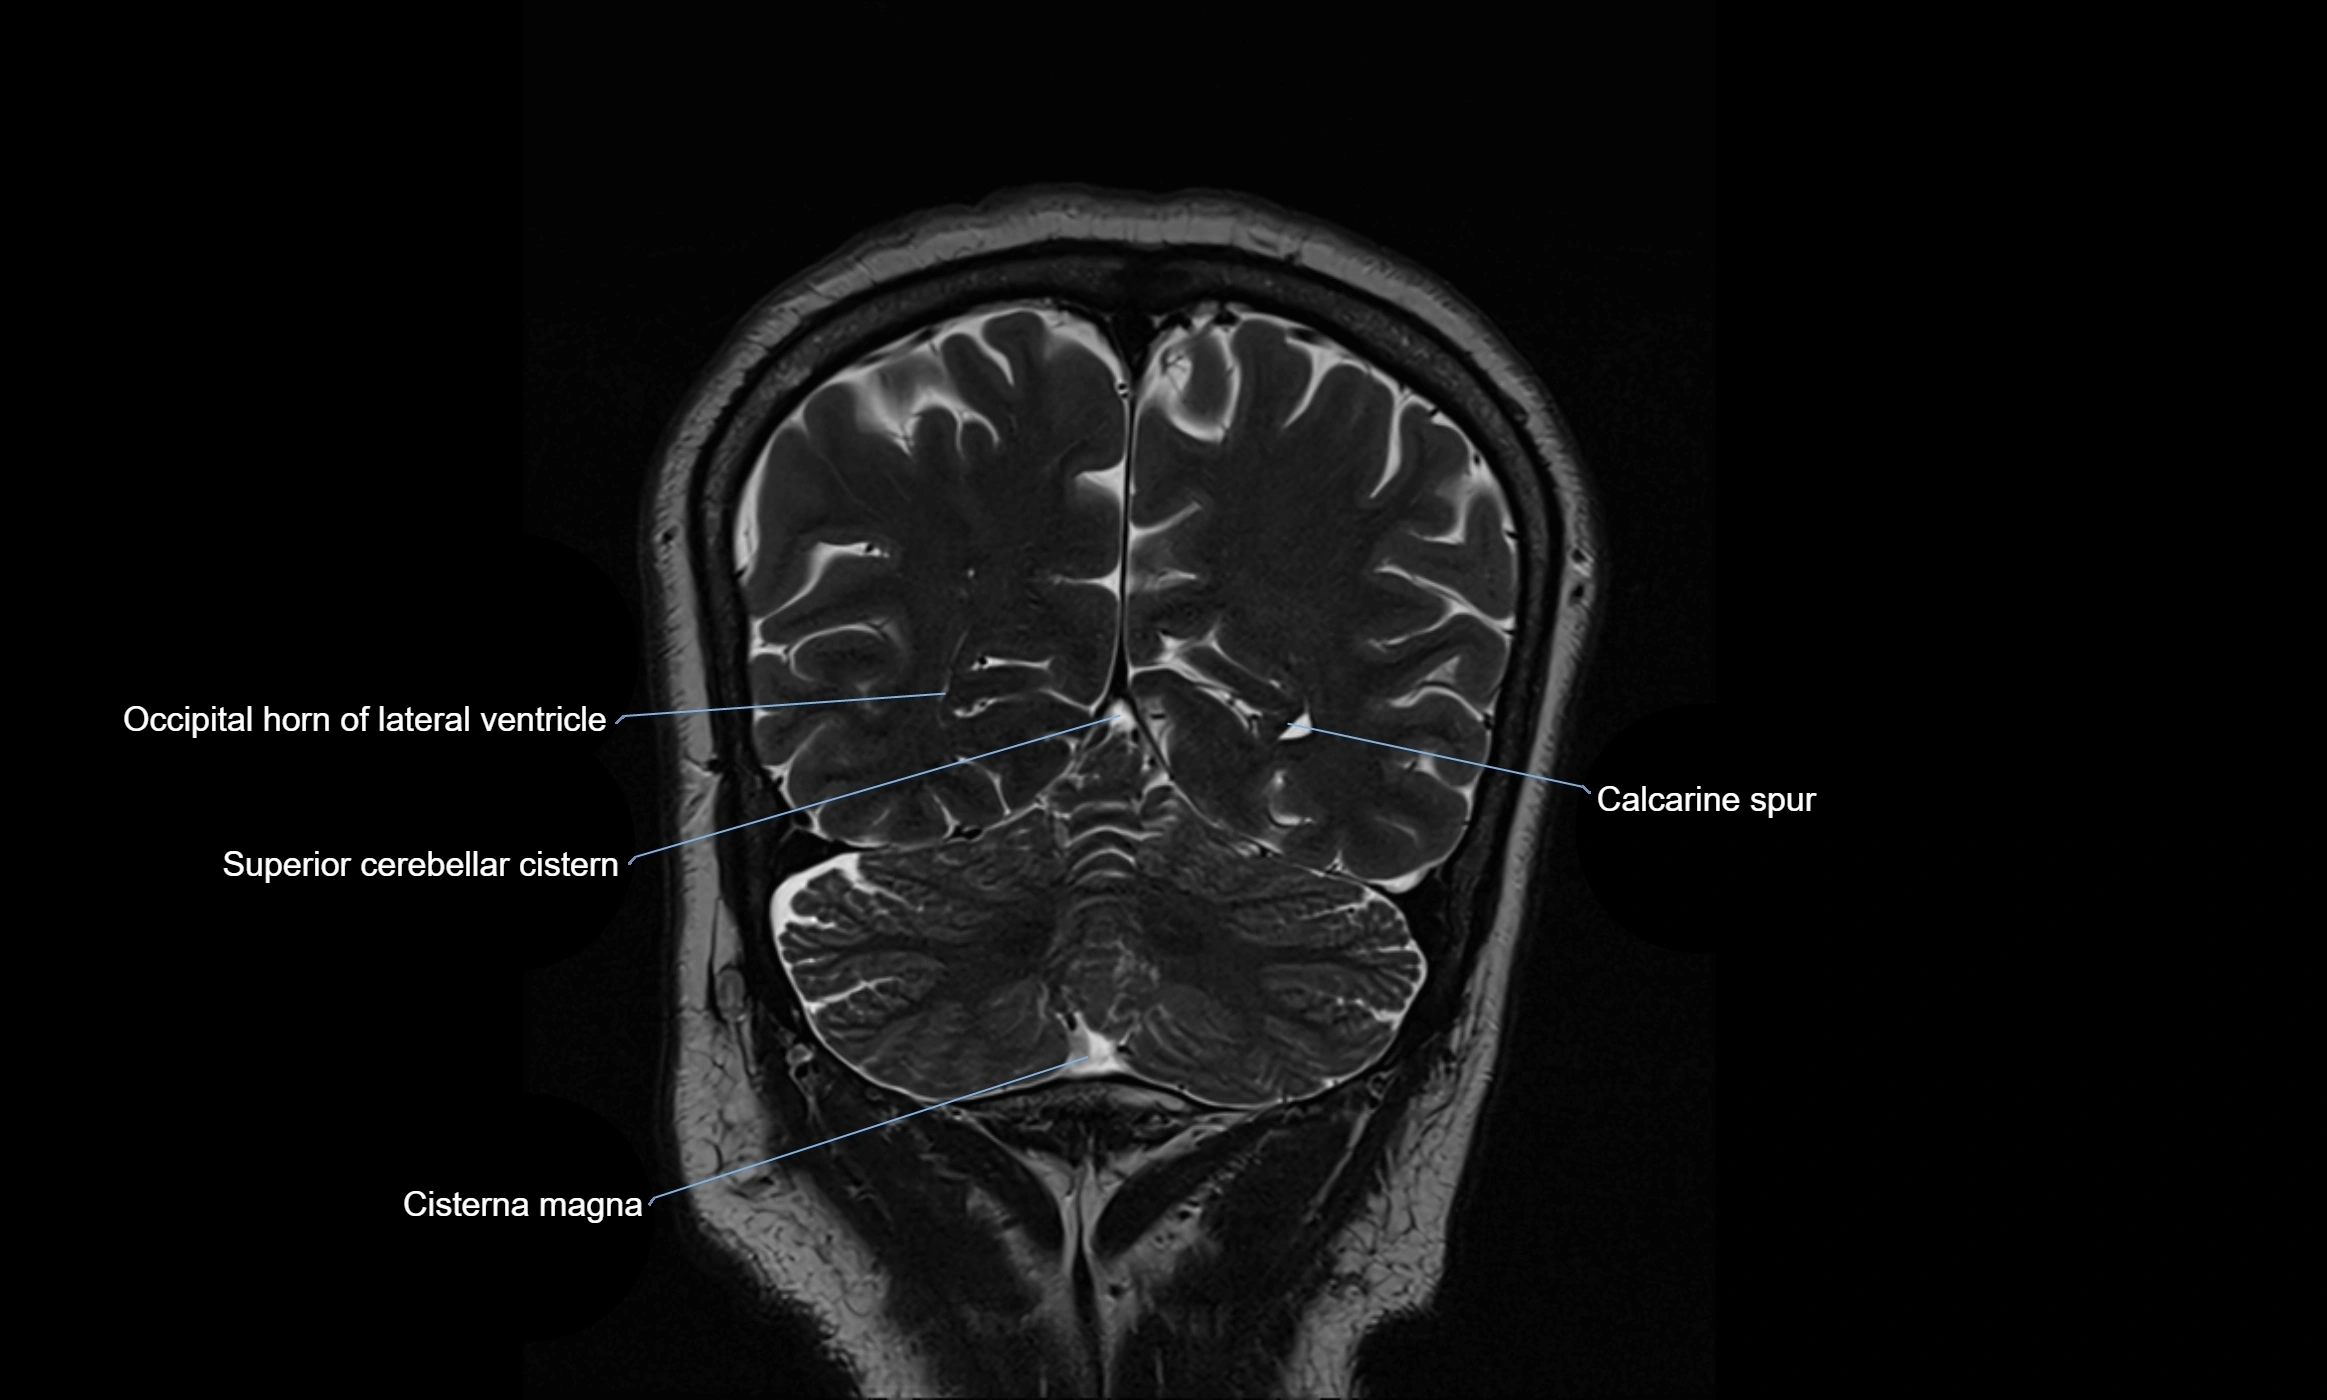

Ambient cistern

The ambient cistern is a paired, narrow, and elongated subarachnoid space located bilaterally along the lateral aspect of the midbrain. It serves as a conduit between the interpeduncular cistern anteriorly and the quadrigeminal cistern posteriorly. This cistern houses critical neurovascular structures, including parts of the posterior cerebral artery, superior cerebellar artery, trochlear nerve (cranial nerve IV), and the basal vein of Rosenthal. It plays an important role in the circulation of cerebrospinal fluid (CSF) and provides an anatomical corridor for various vessels and nerves passing around the midbrain.

MRI images

image